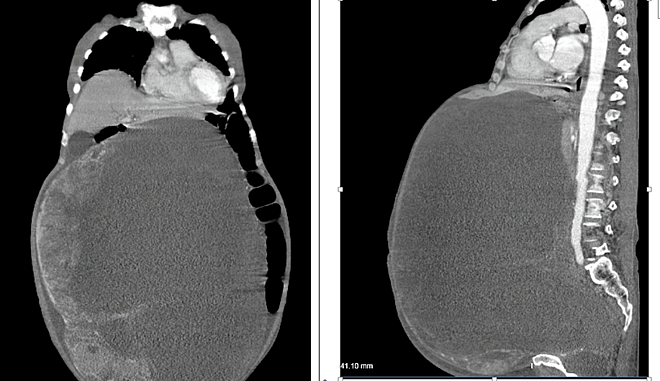

Hình ảnh X-quang cho thấy khối u chiếm gần hoàn toàn ổ bụng bệnh nhân - Ảnh: Vnexpress

Tờ Dân Trí đưa tin, sau khi hội chẩn liên chuyên khoa, bệnh viện quyết định thực hiện cuộc phẫu thuật cắt trọn khối u cho cụ bà. Ngày 19/3, ê kíp bắt tay vào cuộc mổ, khi mở ổ bụng, các bác sĩ phát hiện khối u buồng trứng khổng lồ đã chiếm trọn ổ bụng, chèn ép, đẩy lệch vị trí các bộ phận nội tạng, dính nhiều vào ruột, thành bụng. Sau 2 giờ 30 phút khẩn trương các bác sĩ đã bóc tách thành công đưa khối u có kích thước 30x50 nặng khoảng 30kg ra khỏi cơ thể người bệnh.